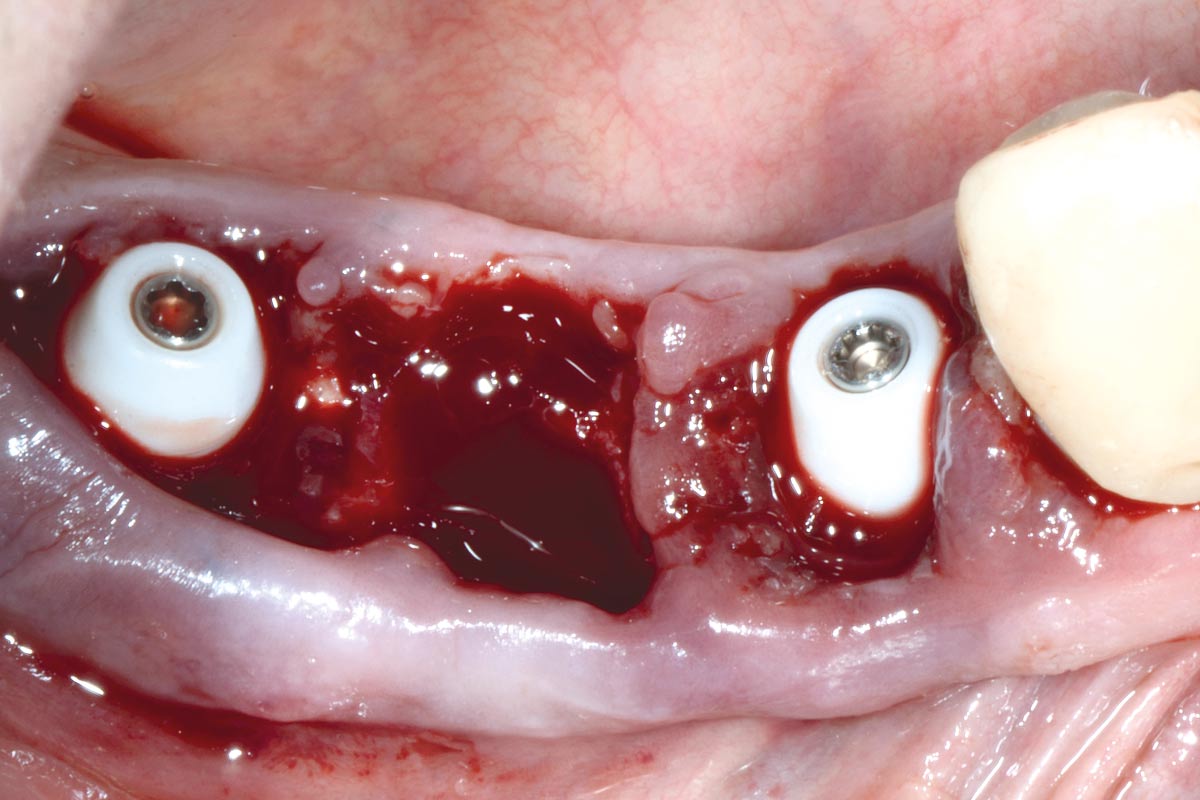

Multiple socket preservation in the mandibular with collacone® max – Dr. D. Jelušić